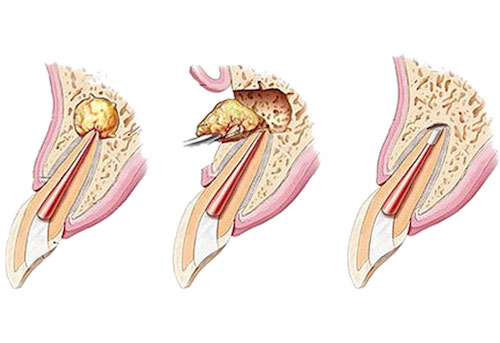

歯の上から治療を行うことで歯が割れてしまうなどのリスクが有るとき、または根尖病変と行って根の先に膿が溜まった状態の場合は、下から治療を行います。

つまり、歯ぐきを切開して、根っこの方から治療を行うということになります。この場合もMTAセメントが役に立ちます。理由としては親水性が高く、血液などの水分があってもきちんと硬化してくれるからです。